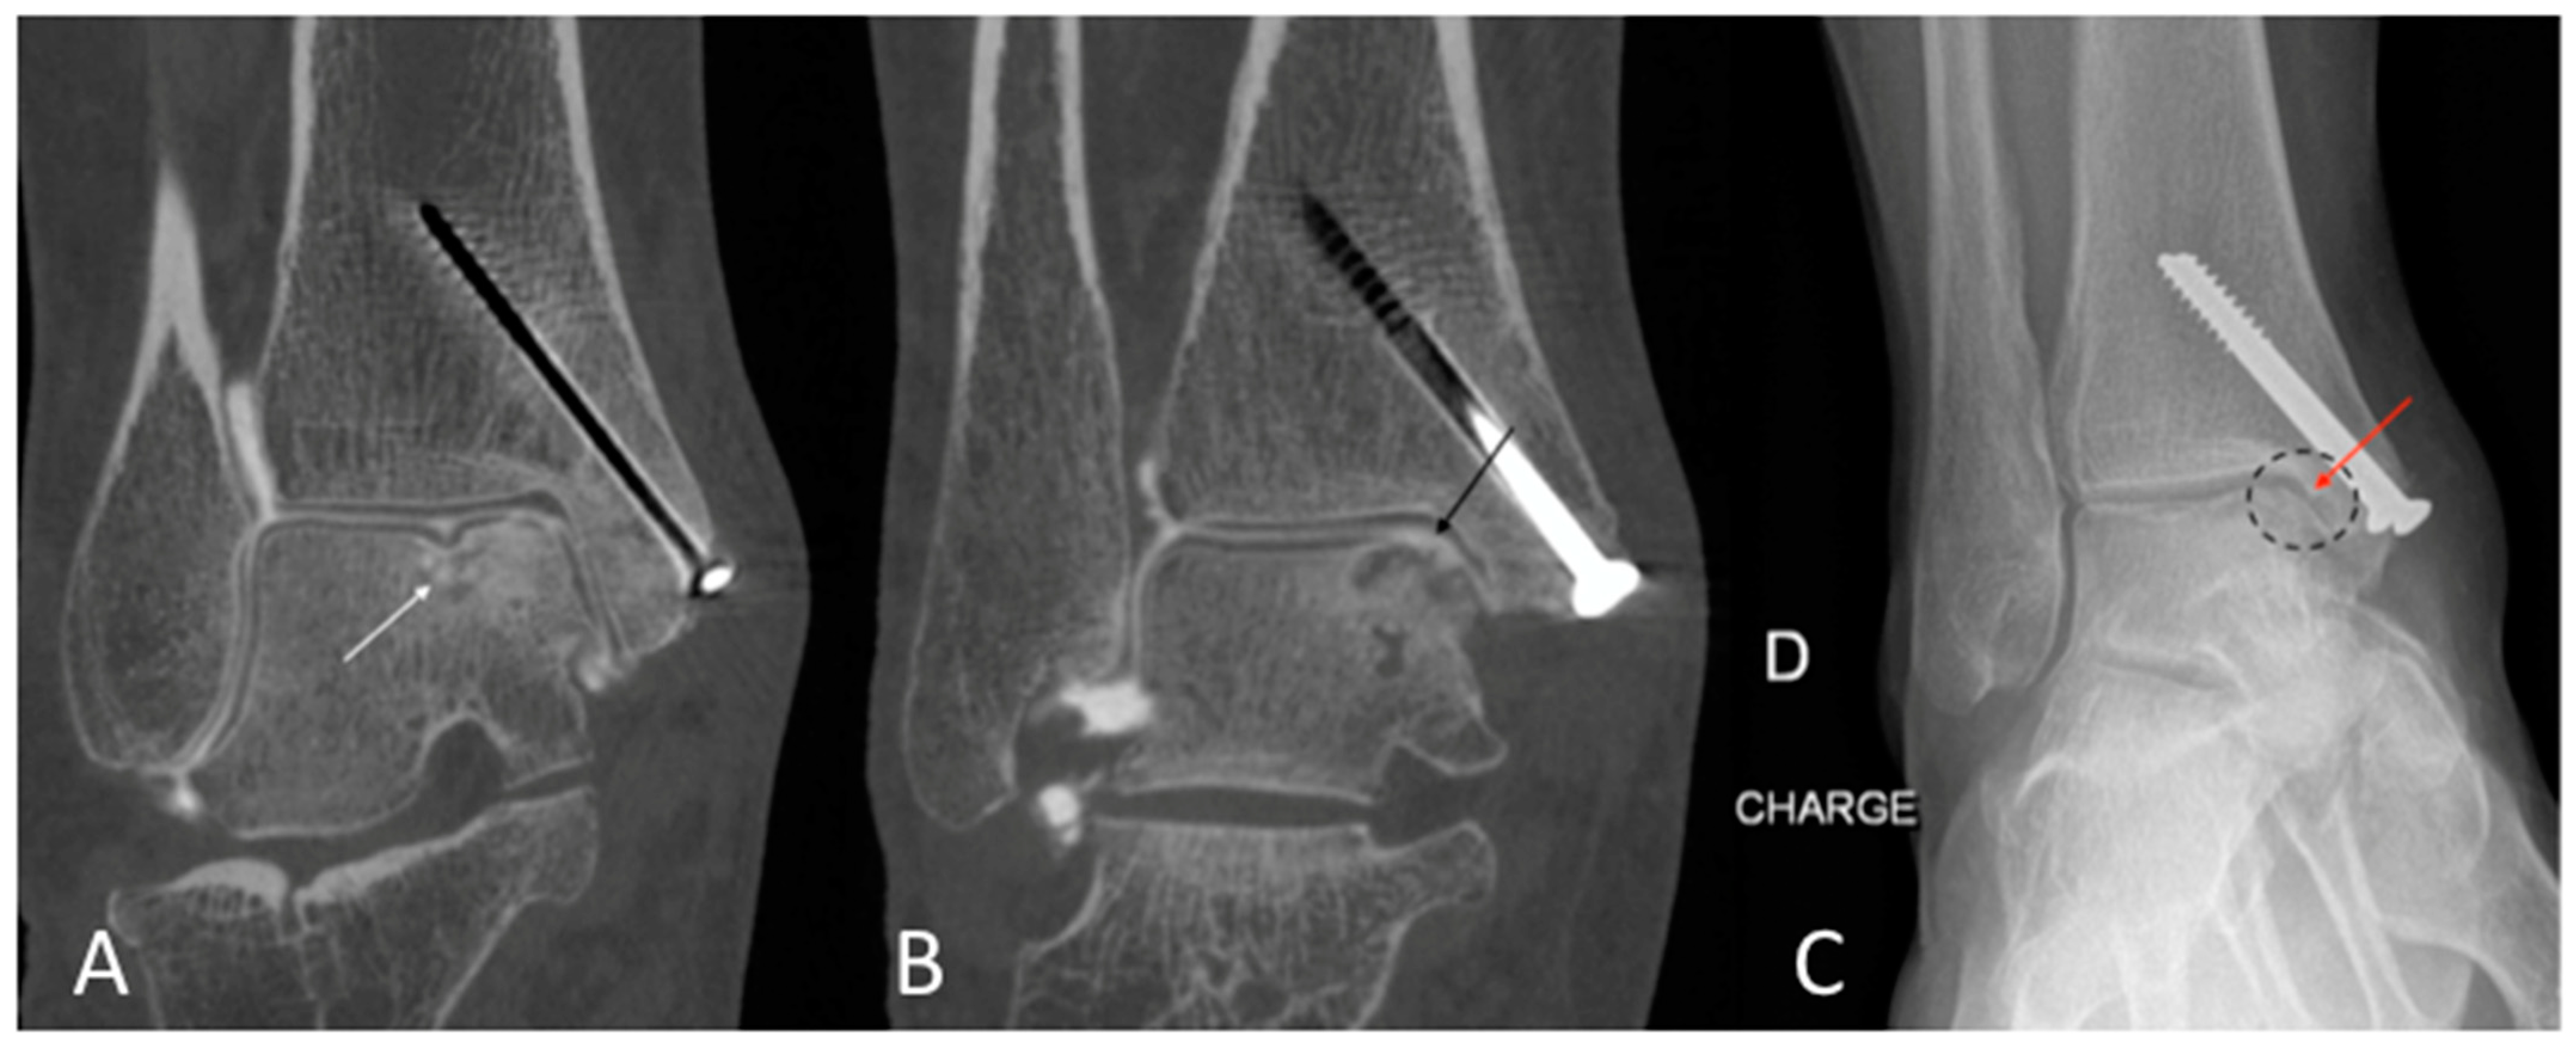

1. Introduction

2.1. Patient Population

2.3. Qualitative Image Analysis for CBCT-A

4. Discussion